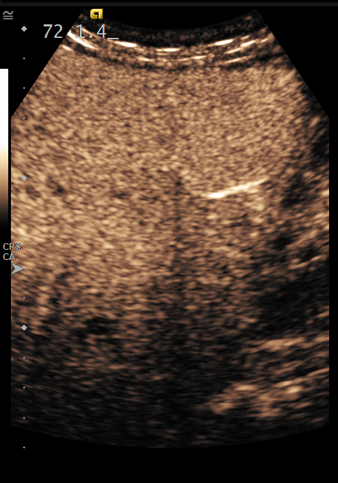

Using Siemens Healthineers ultrasound equipment, these bubbles can be imaged in two distinct contrast-based imaging modes: contrast pulse sequencing and contrast harmonic imaging.

According to Brian, “CPS has a three-pulse sequence that allows us to get deeper into the body. You can see the bubbles a little quicker and they look bigger than they would in the alternate mode. It’s going to provide a better penetration of the ultrasound, making it ideal for most scans involving adults.”

“CHI gives us a higher resolution image for evaluating smaller lesions or lesions with smaller vessels,” said Brian.